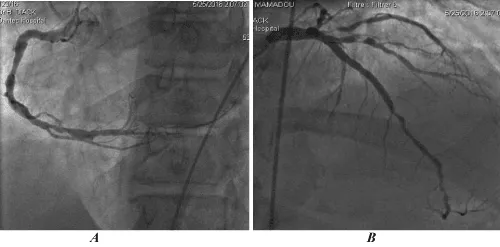

The figure 2 represents a coronary angiography image showing diffuse, multiple and tight lesions.

Figure 2: Image of coronary angiography by right femoral pathway showing diffuse, multiple and tight lesions. A (right coronary artery), B (left coronary artery).